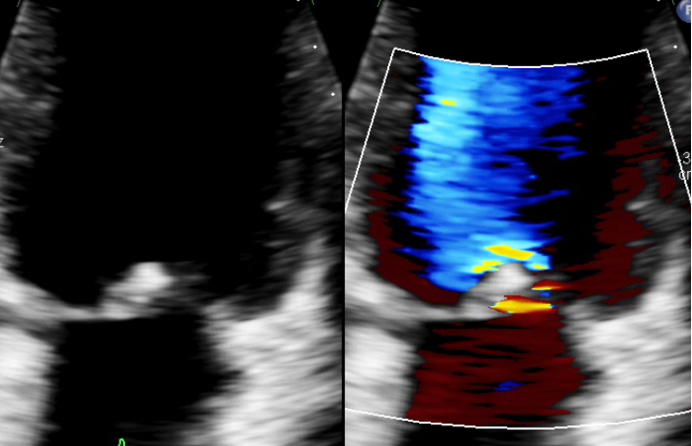

Echocardiography showed severe mitral regurgitation with an anterior leaflet vegetation (Fig. 2). Initial blood cultures were negative for growth, which was likely due to earlier antibiotic administration.

Fig. 2.

Initial transthoracic echocardiography (TTE) with mitral valve regurgitation and echogenic mitral valve lesion. (A) TTE apical 4 chamber view of the left ventricle (LV) revealing an echogenic mobile structure connected to the mitral valve, indicative of vegetation. (B) TTE apical 4 chamber colour doppler demonstrating associated mitral regurgitation (MR), further highlighting the valvular pathology. (C) Transoesophageal echocardiography (TOE) image of a zoomed 4-chamber view, providing a detailed visualization of a flail mitral valve with associated mitral regurgitation, emphasizing the severity of valvular dysfunction. (D) TOE 3D reconstruction displaying a comprehensive view of the vegetation, clearly visualizing its attachment to the ventricular side of the mitral valve.